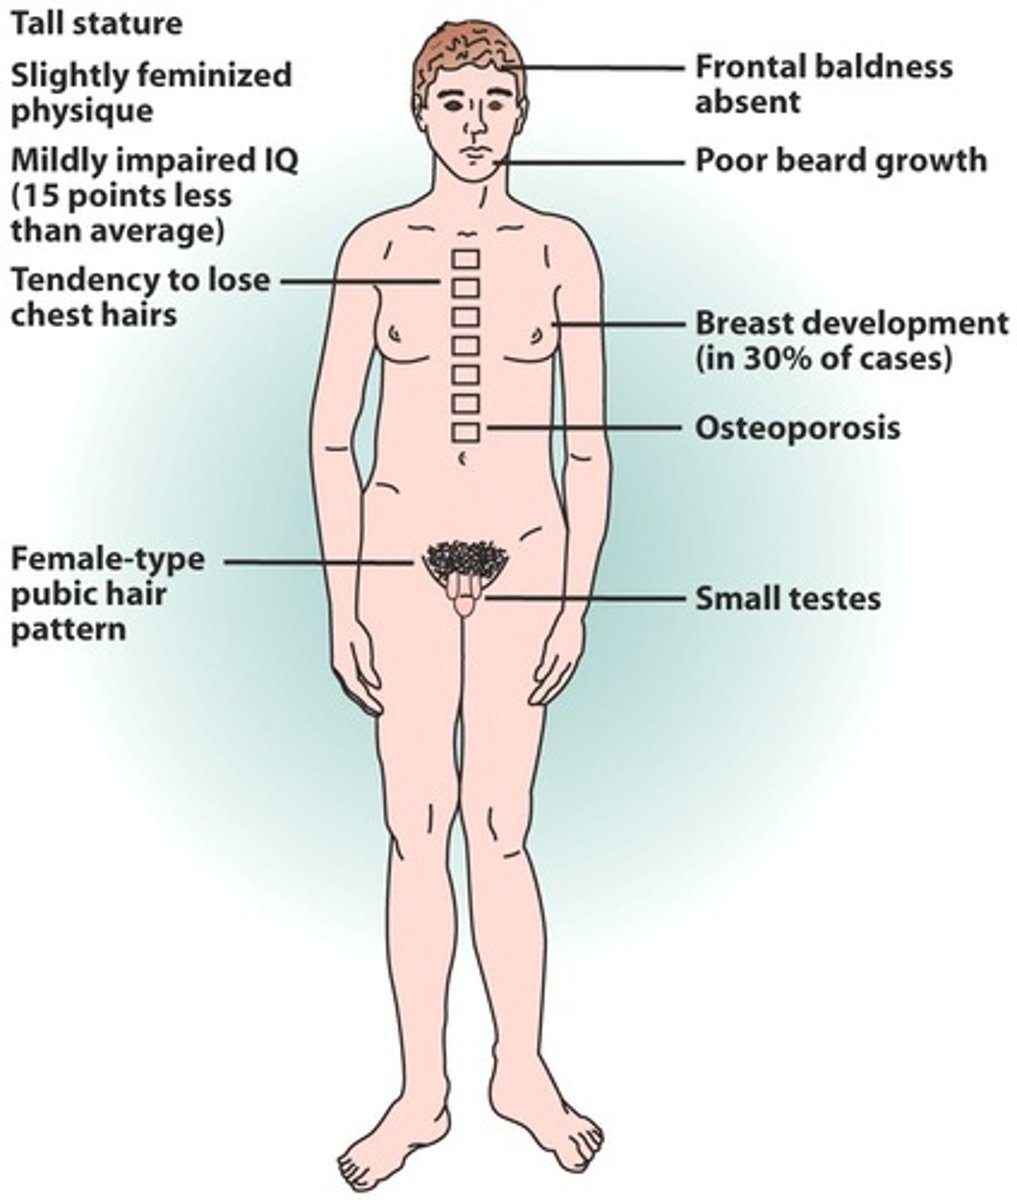

20 y/o tall, thin male presents with gynecomastia and micropenis. What is the likely diagnosis?

Klinefelters (47,XXY)

increased risk for ADHD/Autism